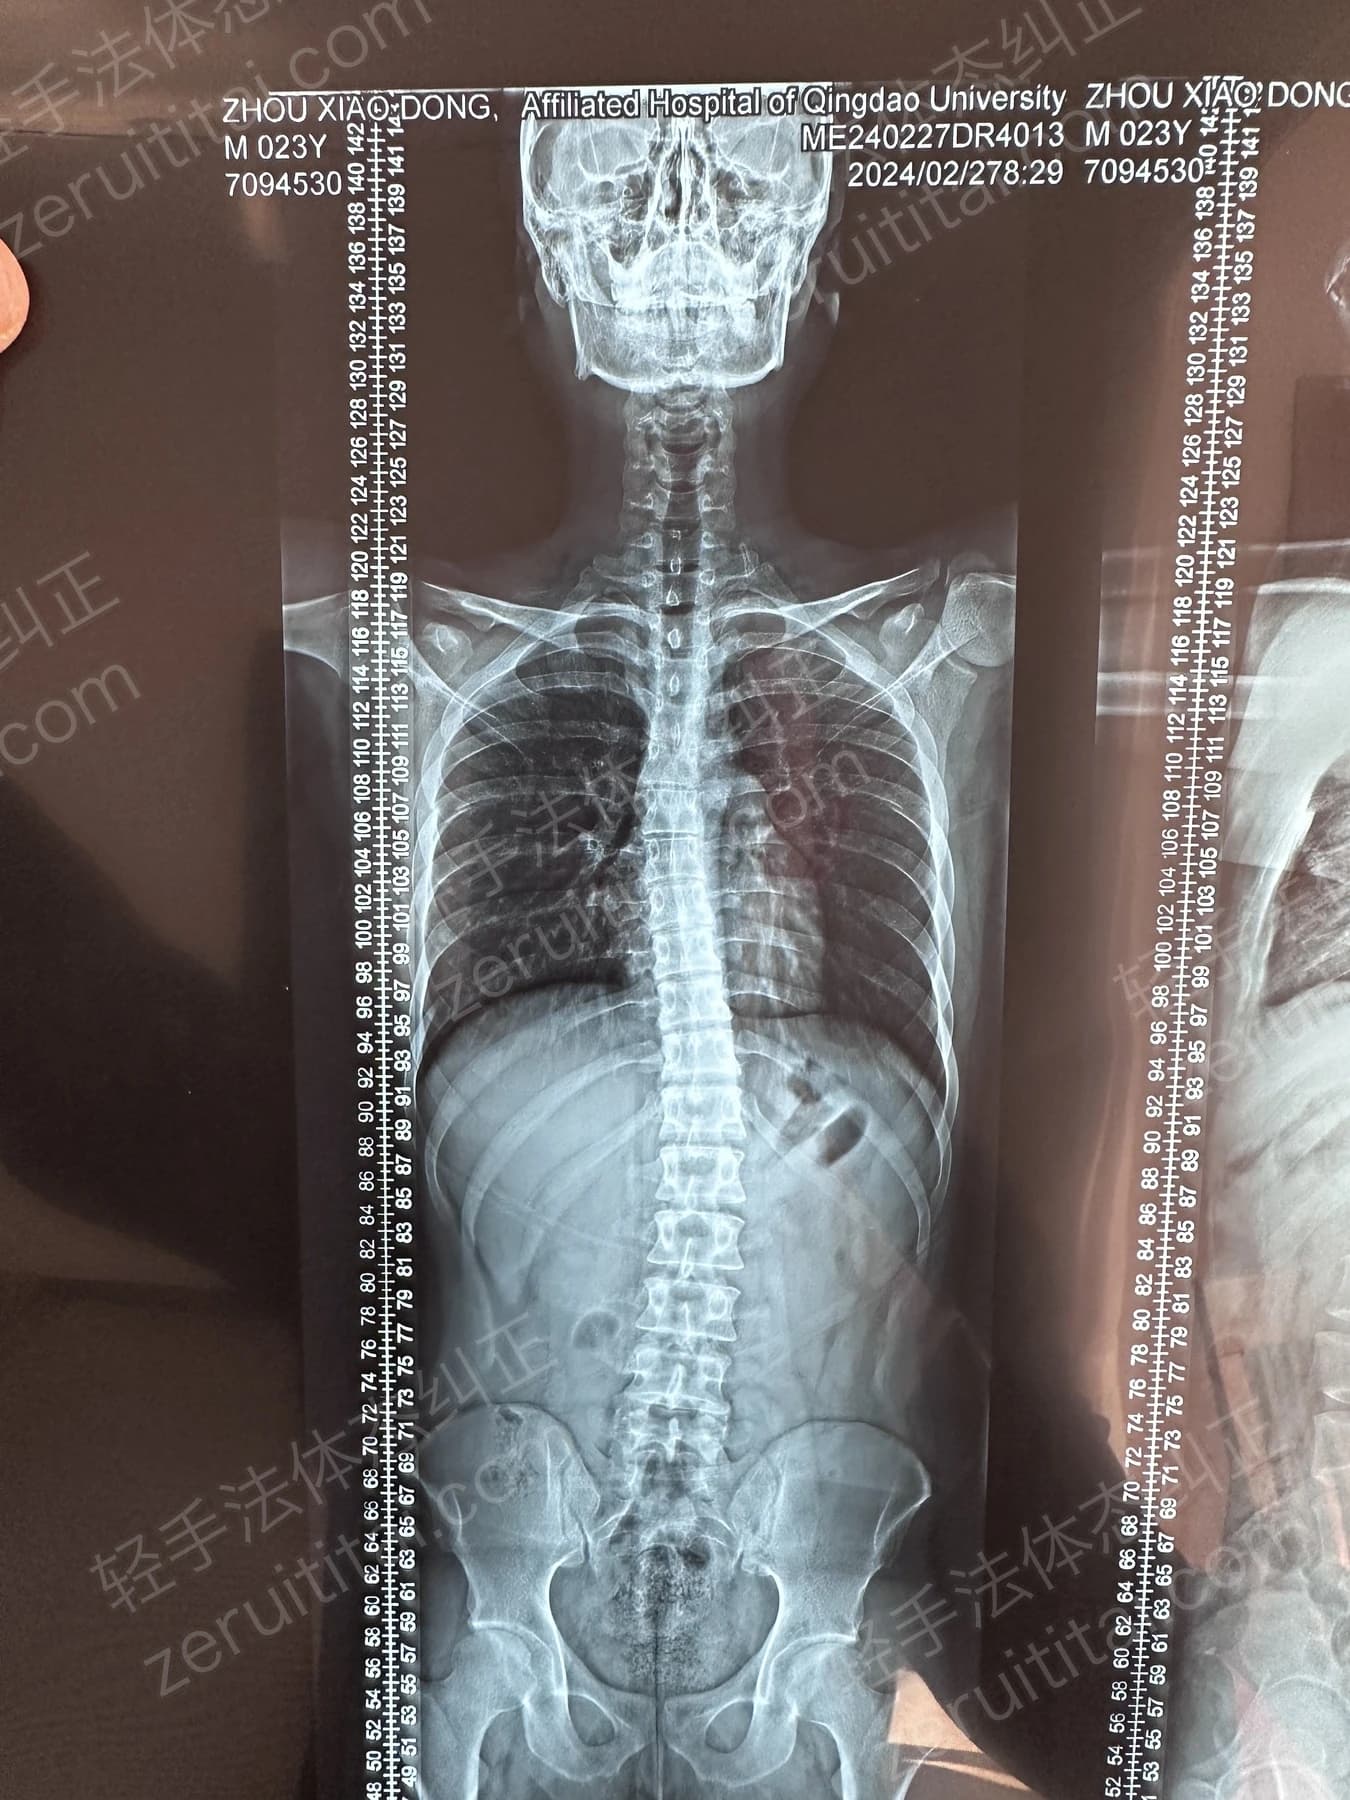

2024.12.18

第 6 次记录

第 6 次记录2024.12.18

正面 X 光